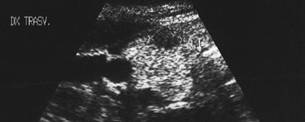

Lob drept , proiectie trasversala si longitudinala.

Femeie 19 ani. Leziune marcant hipoecogen cu intarire posterioara, de 16x20x26mm (4 cc) in lobul drept.

Examen citologic: macrofagi, fara tireocite.